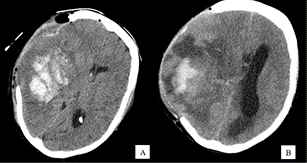

Doente do sexo feminino de 59 anos, não hipertensa, previamente autónoma nas atividades de vida diária e cognitivamente íntegra. Foi admitida no Serviço de Urgência no contexto de cefaleia intensa súbita, apresentando um quadro de hemianopsia homónima e hemiparésia esquerda. Na tomografia computorizada foi identificada uma volumosa hemorragia parenquimatosa cortico-subcortical temporo- fronto-parietal direita. Foi submetida a craniectomia descompressiva emergente. Apresentou, posteriormente, uma evolução clínica e funcional favorável, tendo sido transferida ao 66o dia para enfermaria de MFR. 17 dias depois, iniciou um quadro indolente de deterioração do estado de consciência, com progressiva sonolência e prostração, inviabilizando a participação no programa de reabilitação. Dado o agravamento do estado neurológico, foi realizado novo estudo neuro-imagiológico, o qual identificou uma volumosa lesão expansiva com padrão de realce necrótico-quístico, de provável etiologia neoplásica (primária da série glial ou secundária).